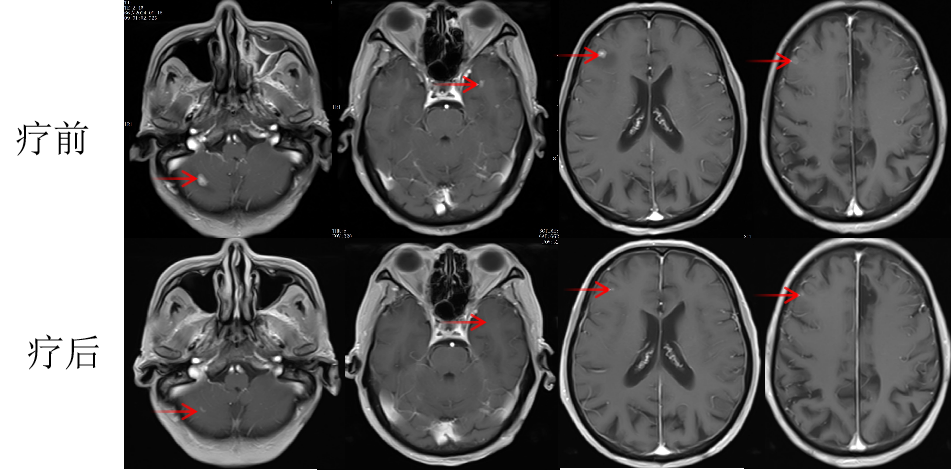

張老太,70歲, 2024年8月因頭暈頭痛,頻繁嘔吐等癥狀入院。頭部磁共振檢查顯示,顱內(nèi)多發(fā)腦轉(zhuǎn)移瘤病灶(見圖)。同時(shí),患者胸部CT檢查可見肺內(nèi)多發(fā)較大腫瘤病灶(見圖)?;颊哂?024年8月20日行CT引導(dǎo)肺腫物穿刺活檢。病理診斷為肺腺癌。綜合診斷為肺腺癌IVB期,腦、肺內(nèi)、右腎上腺多發(fā)轉(zhuǎn)移?;颊哌M(jìn)一步行腫瘤組織基因檢測(cè)和免疫檢查點(diǎn)分子——細(xì)胞程序性死亡配體1(PDL1)檢測(cè)。

圖注:磁共振檢查,小腦蚓部、右側(cè)基底節(jié)-放射冠異常信號(hào)影,考慮轉(zhuǎn)移瘤,伴灶周水腫。

患者于2024年08月20開始接受頭部放療。采用最新一代智慧化精準(zhǔn)放療系統(tǒng)——Halcyon“速銳刀”,成功控制患者全部顱內(nèi)病灶,過程順利,沒有明顯副反應(yīng)發(fā)生。患者基因檢測(cè)結(jié)果為陰性,沒有找到具有靶向治療藥物的突變基因。此外,患者年齡較大,體質(zhì)較弱,全身多發(fā)轉(zhuǎn)移病灶,為治療帶來了巨大的挑戰(zhàn)。然而,患者PDL1檢測(cè)顯示,PDL1高表達(dá)(PD-L1 TPS=98%),提示免疫治療有效率較高。潘振宇教授團(tuán)隊(duì)為患者制定了個(gè)體化精準(zhǔn)腫瘤治療方案,僅僅每3周應(yīng)用1次免疫治療藥物。經(jīng)過3次治療后復(fù)查,患者肺內(nèi)病灶顯著縮退,顱內(nèi)病灶縮退。治療過程中,僅出現(xiàn)一過性皮疹。目前患者恢復(fù)良好,生活完全自理。

圖注:治療后復(fù)查磁共振顯示,顱內(nèi)病灶明顯縮小。